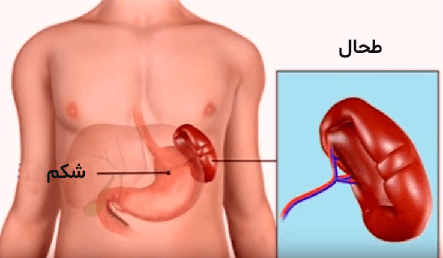

عکس داخل شکم انسان. در این همان طور که مشخص است شکم حالت بیضی شکل پیداکرده و این بیضی که کناره های شکم کشیده شده است. تعداد سلول های بدن انسان حدود ۳۷ ۲ تریلیون تخمین زده شده اند. Abdomen که در زبان عامه به غلط به آن دل نیز می گویند در آناتومی به قسمتی از تنه گفته می شود که مابین دیافراگم از بالا و سطح فوقانی لگن خاصره از پایین قرار دارد. ربات دیدنی ربات انساننمای چینی به صورت یک دختر جوان ساخته شده و جیا جیا نامگذاری شده است این ربات طوری برنامهریزی شده که میتواند صحبت کند و احساسات خود را از طریق تغییرات در چهره حالات.

شکل دوم شکم مادری را نشان می دهد که جنین دختر دارد. وحشت مادر از عکس سونوگرافی جنین داخل شکمش عکس. تصاویر جالب از داخل مغز و نخاع انسان آخرین نیوز. بدن انسان کل ساختار انسان است که سر گردن تنه سینه و شکم دو بازو و دست ها و دو ساق پا و پاها را شامل می شود.

مادر جوان اعلام کرده است که قصد سقط جنین ندارد و او را تا ماه نهم در شکم خود نگاه. درد شکم ناف درد شکم و معده علائم درد شکم سمت راست درمان درد شکم نفخ و درد شکم. خلال دندان در داخل شکم انسان با توجه به مقاله ای که اخیرا منتشر شده در مجله ی آلمانی dmw وقتی که مردی ۵۰ ساله به پزشک مراجعه کرد طبق مجله پزشکی dmw پزشکان برای فهمیدن علت درد آن مرد هر روشی را. عکس سونوگرافی جنین شبیه جمجمه انسان.